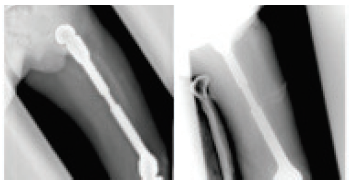

[사진] 성장에 따라 다리 길이를 맞추기 위해 종양 대치물의 길이를 늘려 준 사진

골종양은 수술, 항암 화학 요법 등의 치료가 끝난 후에도 정기적인 진료가 필요합니다. 이 때에는 재발 여부나 감염 여부, 종양 대치물의 상태 등이 주요 관심사가 되며, 이를 위해 환자 검진, X-ray나 MRI 등의 영상 검사, 피검사 등을 시행하게 됩니다. 소아 골종양 환자의 경우 수술 후 환자의 성장에 따라 사지 길이의 차이가 발생할 수 있는데, 이 경우 종양 대치물의 길이를 늘리는 수술이나 성장판을 조절하는 수술 등이 필요할 수 있습니다. 또한 종양 대치물의 기계적 수명이 다한 경우 새로운 대치물로 바꾸는 수술이 필요할 수 있습니다.